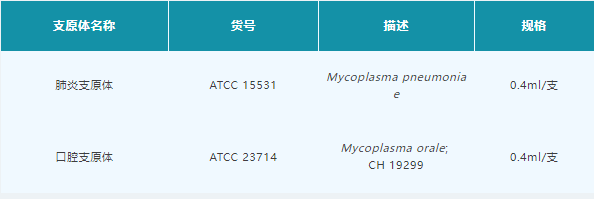

ATCC支原体菌株

在中国药典2020版三部:3301 支原体检查法中,明确标明了支原体检测时使用的菌株为ATCC来源的菌株,产品信息如下: